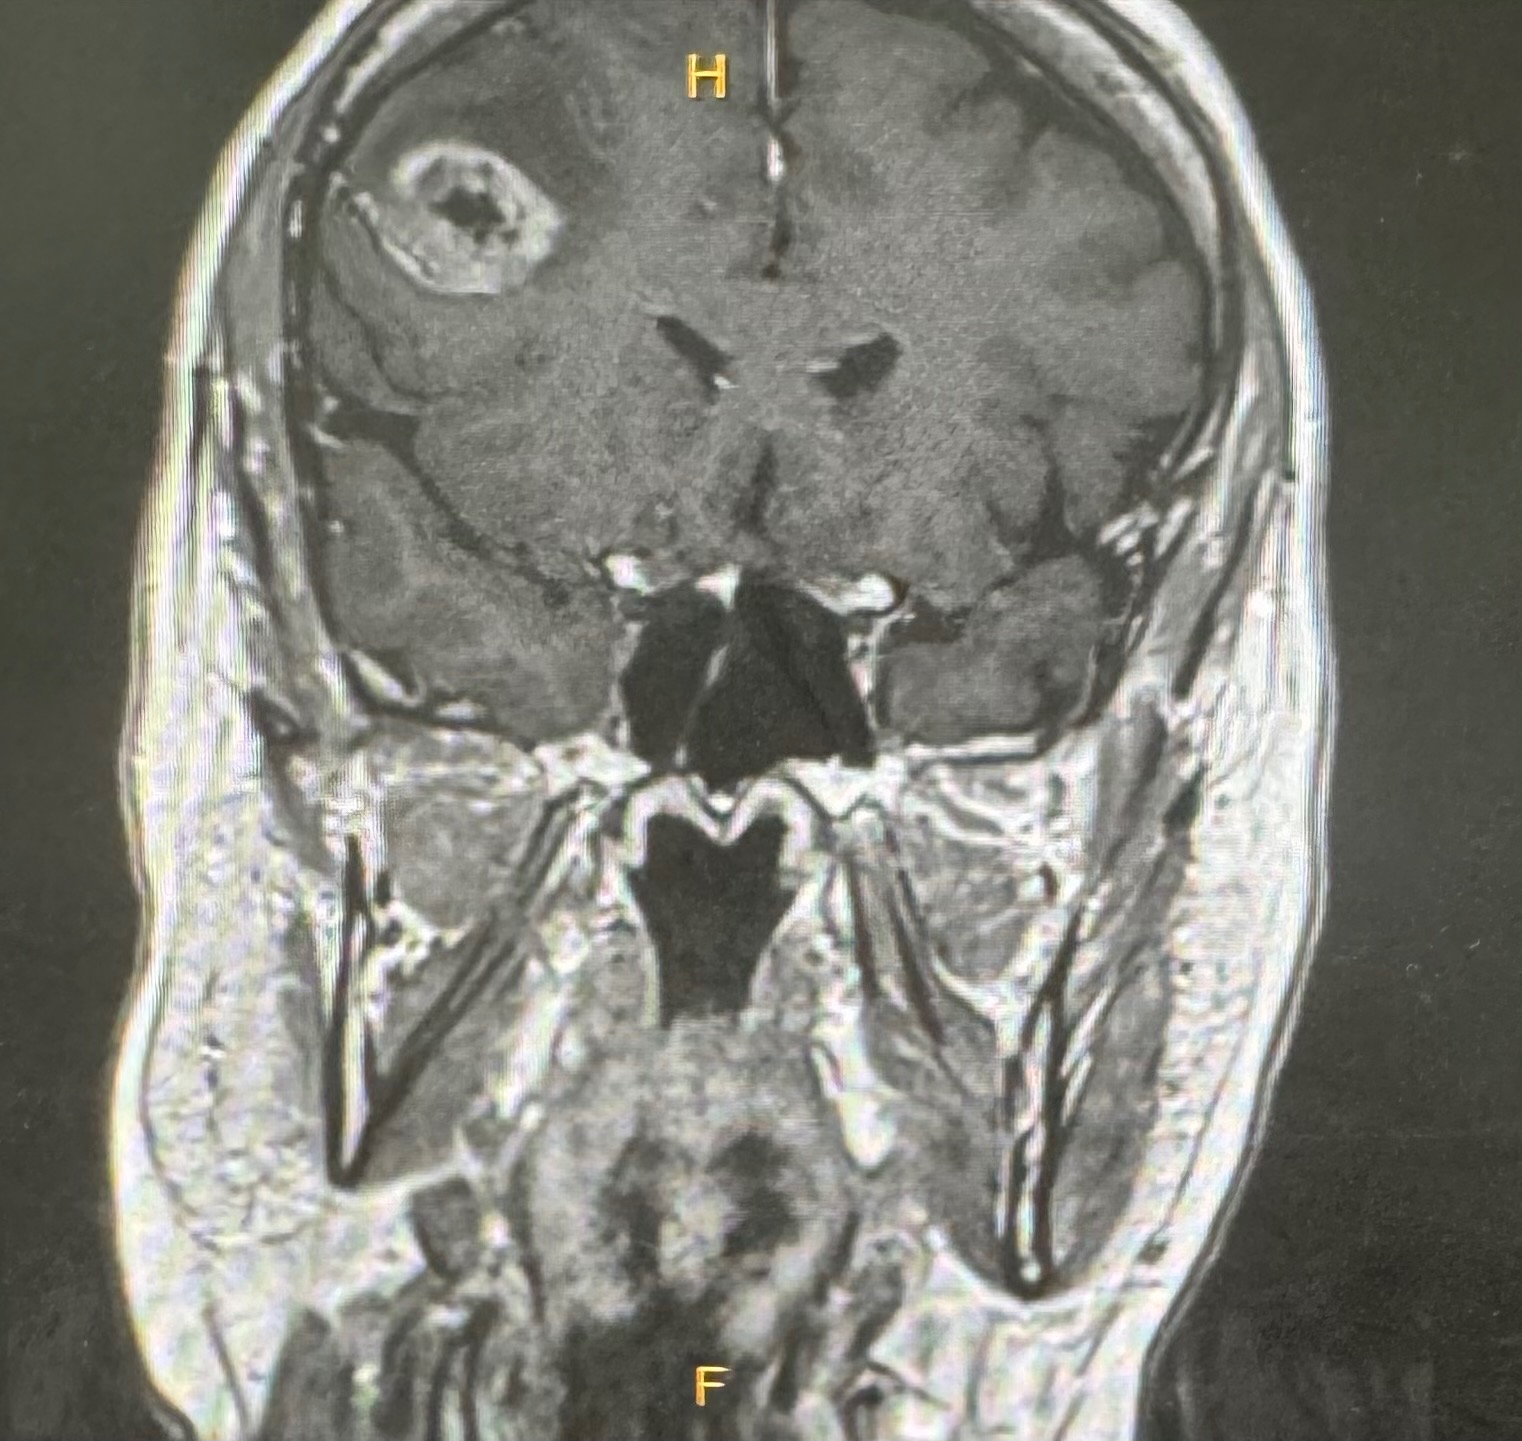

Today, I find myself once again in the ring vs. cancer. This time it is Glioblastoma, an aggressive brain cancer. It is completely unrelated to the preciosa breast cancer. Fun huh?! - 47 yrs young and I have developed 2 unrelated types of cancer. I have hope and faith in the power of healing, and I feel strong and ready for a good fight against this new challenge.

After a successful surgery in October to remove the tumor from my right frontal lobe, I will now continue with the standard treatment (radiation and chemotherapy-here we go again!) This time, the fight’s focus is to to stave off recurrence. To do that I am exploring Integrative oncology treatments along side the standard treatments including a promising and personalized peptide vaccine from the CeGat institute in Germany, as well as other therapies to support my immune system and overall well-being. These approaches offer real hope for extending both the quality and length of my life — but they come with high costs that are not covered by insurance.